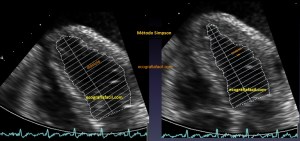

141. Mediciones de los planos paraesternales.